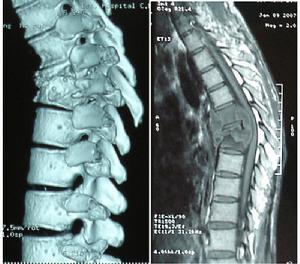

胸椎平掃胸椎平掃是為了明確胸椎病變而做的CT的基本檢查方法,對於病變的定位、判斷病變的性質均較可靠。 脊柱疾病尤其腫瘤種類繁多,性質各異,影像學表現多種多樣,一些類腫瘤的影像學改變的脊柱疾患,如不典型結核、感染、骨質疏鬆症等疾患,更加難以做出明確診斷。因此,病理診斷成為確診的主要依據,病變組織活檢是取得病理的主要手段。病理結果結合患者臨床表現、體徵、影像學表現、實驗室檢查,可以得出比較正確的結論,對患者治療方案的制定具有決定性的指導意義。活檢可以通過切除活檢、切開活檢、閉合活檢進行,一般情況下對疑為惡性腫瘤的多採用閉合活檢和切開活檢,切開活檢易於獲取足夠的組織做出診斷,但有較大的污染周圍組織、增加轉移機會的危險。CT以其良好的密度解析度和空間解析度,為人體深部各部位穿刺活檢提供精確導航,從2003年開始開展脊柱病變CT引導下穿刺活檢檢查,收到了良好的效果